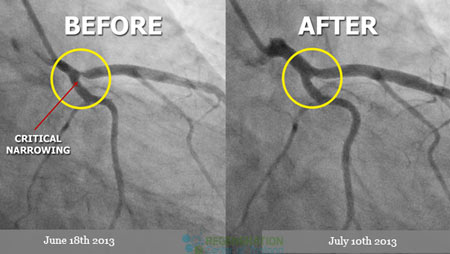

Plaque is produced because of the cholesterol, calcium, fat, and other substances found in the blood. When the plaque starts to build up in your arteries, you get diagnosed with a disease called atherosclerosis. The building up of the plaque takes place over many years. As time passes by, the plaque narrows your coronary arteries and thus hardens. This is the cause of the limited oxygen-rich blood in the heart.

The plague-infested region can also rupture, or break open. This forms a blood clot on the surface of the plaque. When this worsens, and the blood clot becomes more prominent, this disturbs the blood flow in the coronary artery (coronary atherosclerosis.) Moreover, angina or a heart attack might happen if your heart does not receive a regular flow of blood and fresh oxygen. Angina is a severe discomfort in the chest. It might feel like there is a pressure or squeezing inside your chest. The pain also might happen inside your neck, shoulders, arms, back or, jaw. Angina discomfort might even really feel like indigestion.

Repairing the heart with stem cells offers a new alternative,non-surgical treatment option and can help reverse heart disease. [3] The impact of enhanced stem cell therapies are better understood now more than ever, and The Heart Regeneration Center offers a unique and effective cardiac regeneration protocol depending on patients needs. Cardiac cell transplants and targeted paracrine signaling help rebuild a patient’s heart tissue by utilizing clinical grade hematopoietic mesenchymal stem cells. For most elderly patients or those with severe physical limitations, a combination of therapy with allogeneic cells maybe required.  This option is only available for patients whose own cells are not sufficient or impotent due to age or other diseases. The stem cells are immune-system compatible and expanded from cardiosphere-derived stem cells to help assist replenish/replace damaged heart cells and reverse symptoms of coronary atherosclerosis and coronary heart disease. [4] The enriched stem cells are then placed them back into the heart generally via a process known as homing using multiple stage delivery over two weeks.